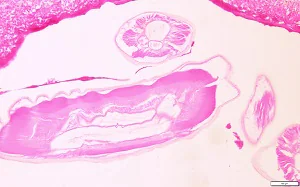

Dirofilaria immitis is usually diagnosed by the finding of the distinctive coin lesions on chest X-rays. The species that produce subcutaneous nodules are diagnosed by the finding of adult worms in biopsy specimens of these nodules. The morphologic features of the cuticle, musculature, and lateral chords are important criteria for identifying Dirofilaria. Worms removed from the eye are usually diagnosed by external features of the cuticle; worms may also be processed by routine histologic methods to study the internal structures. There are currently no serologic or molecular methods available in the United States for diagnosis of human dirofilariasis.